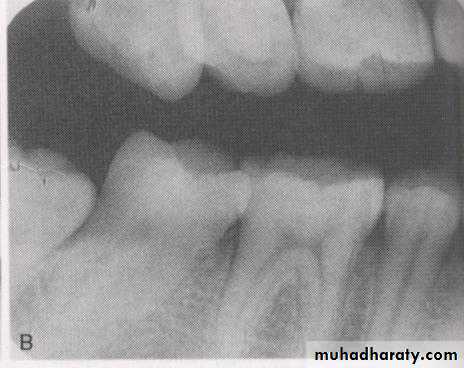

Is the difference in the degree of blackness between adjacent area on dental radiograph. Densities on the radiograph are not simply black and white but encompass multiple shade of gray called scale of contrast.

High contrast image (short scale contrast) would be black and white with few gray shades.

Low contrast image (long scale contrast) usually contain a wide range of shades of gray .INFLUENCING FACTORS